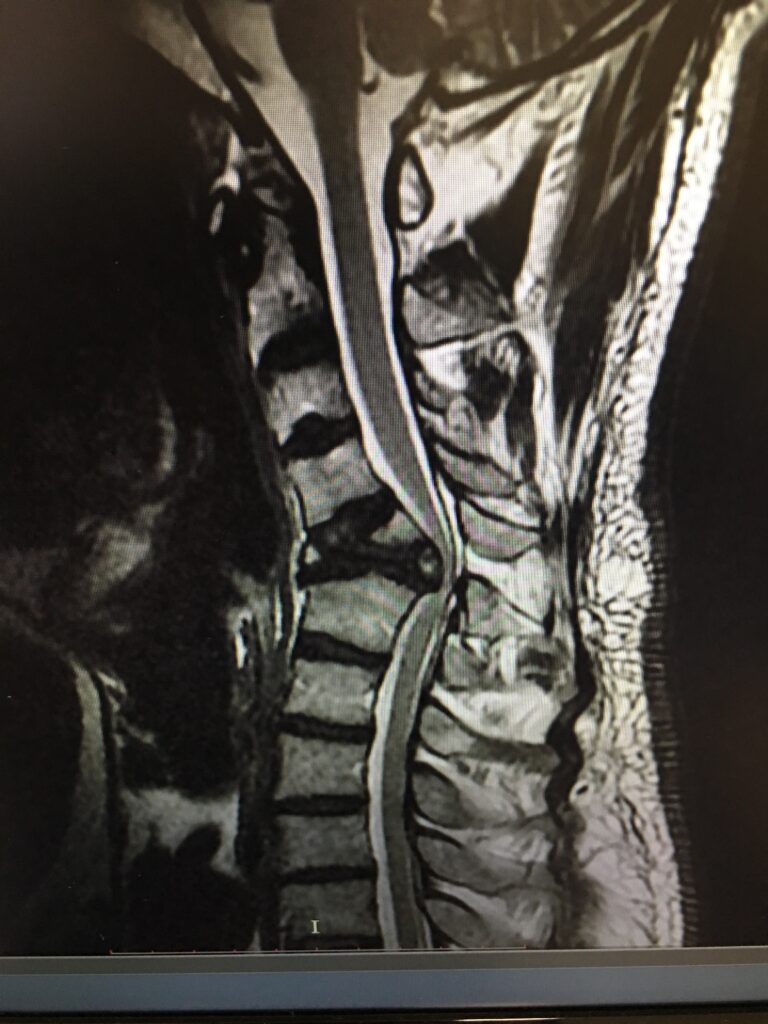

Patologias de Coluna

Hérnia de Disco

Tumor de Coluna

Descompressão Medular